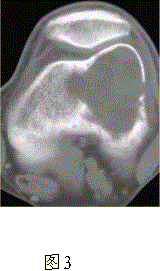

问题 患者女,35岁,左膝关节隐痛1年余,近1周加重,活动后明显疼痛。查体:左股骨下端外侧肿胀,压痛。行左膝关节正侧位CR,并行左膝关节CT扫描,见下图。 对本病例,应首先考虑的诊断是

选项 A.动脉瘤样骨囊肿 B.骨囊肿 C.成软骨细胞瘤 D.骨结核 E.骨巨细胞瘤 F.非骨化性纤维瘤

答案 E